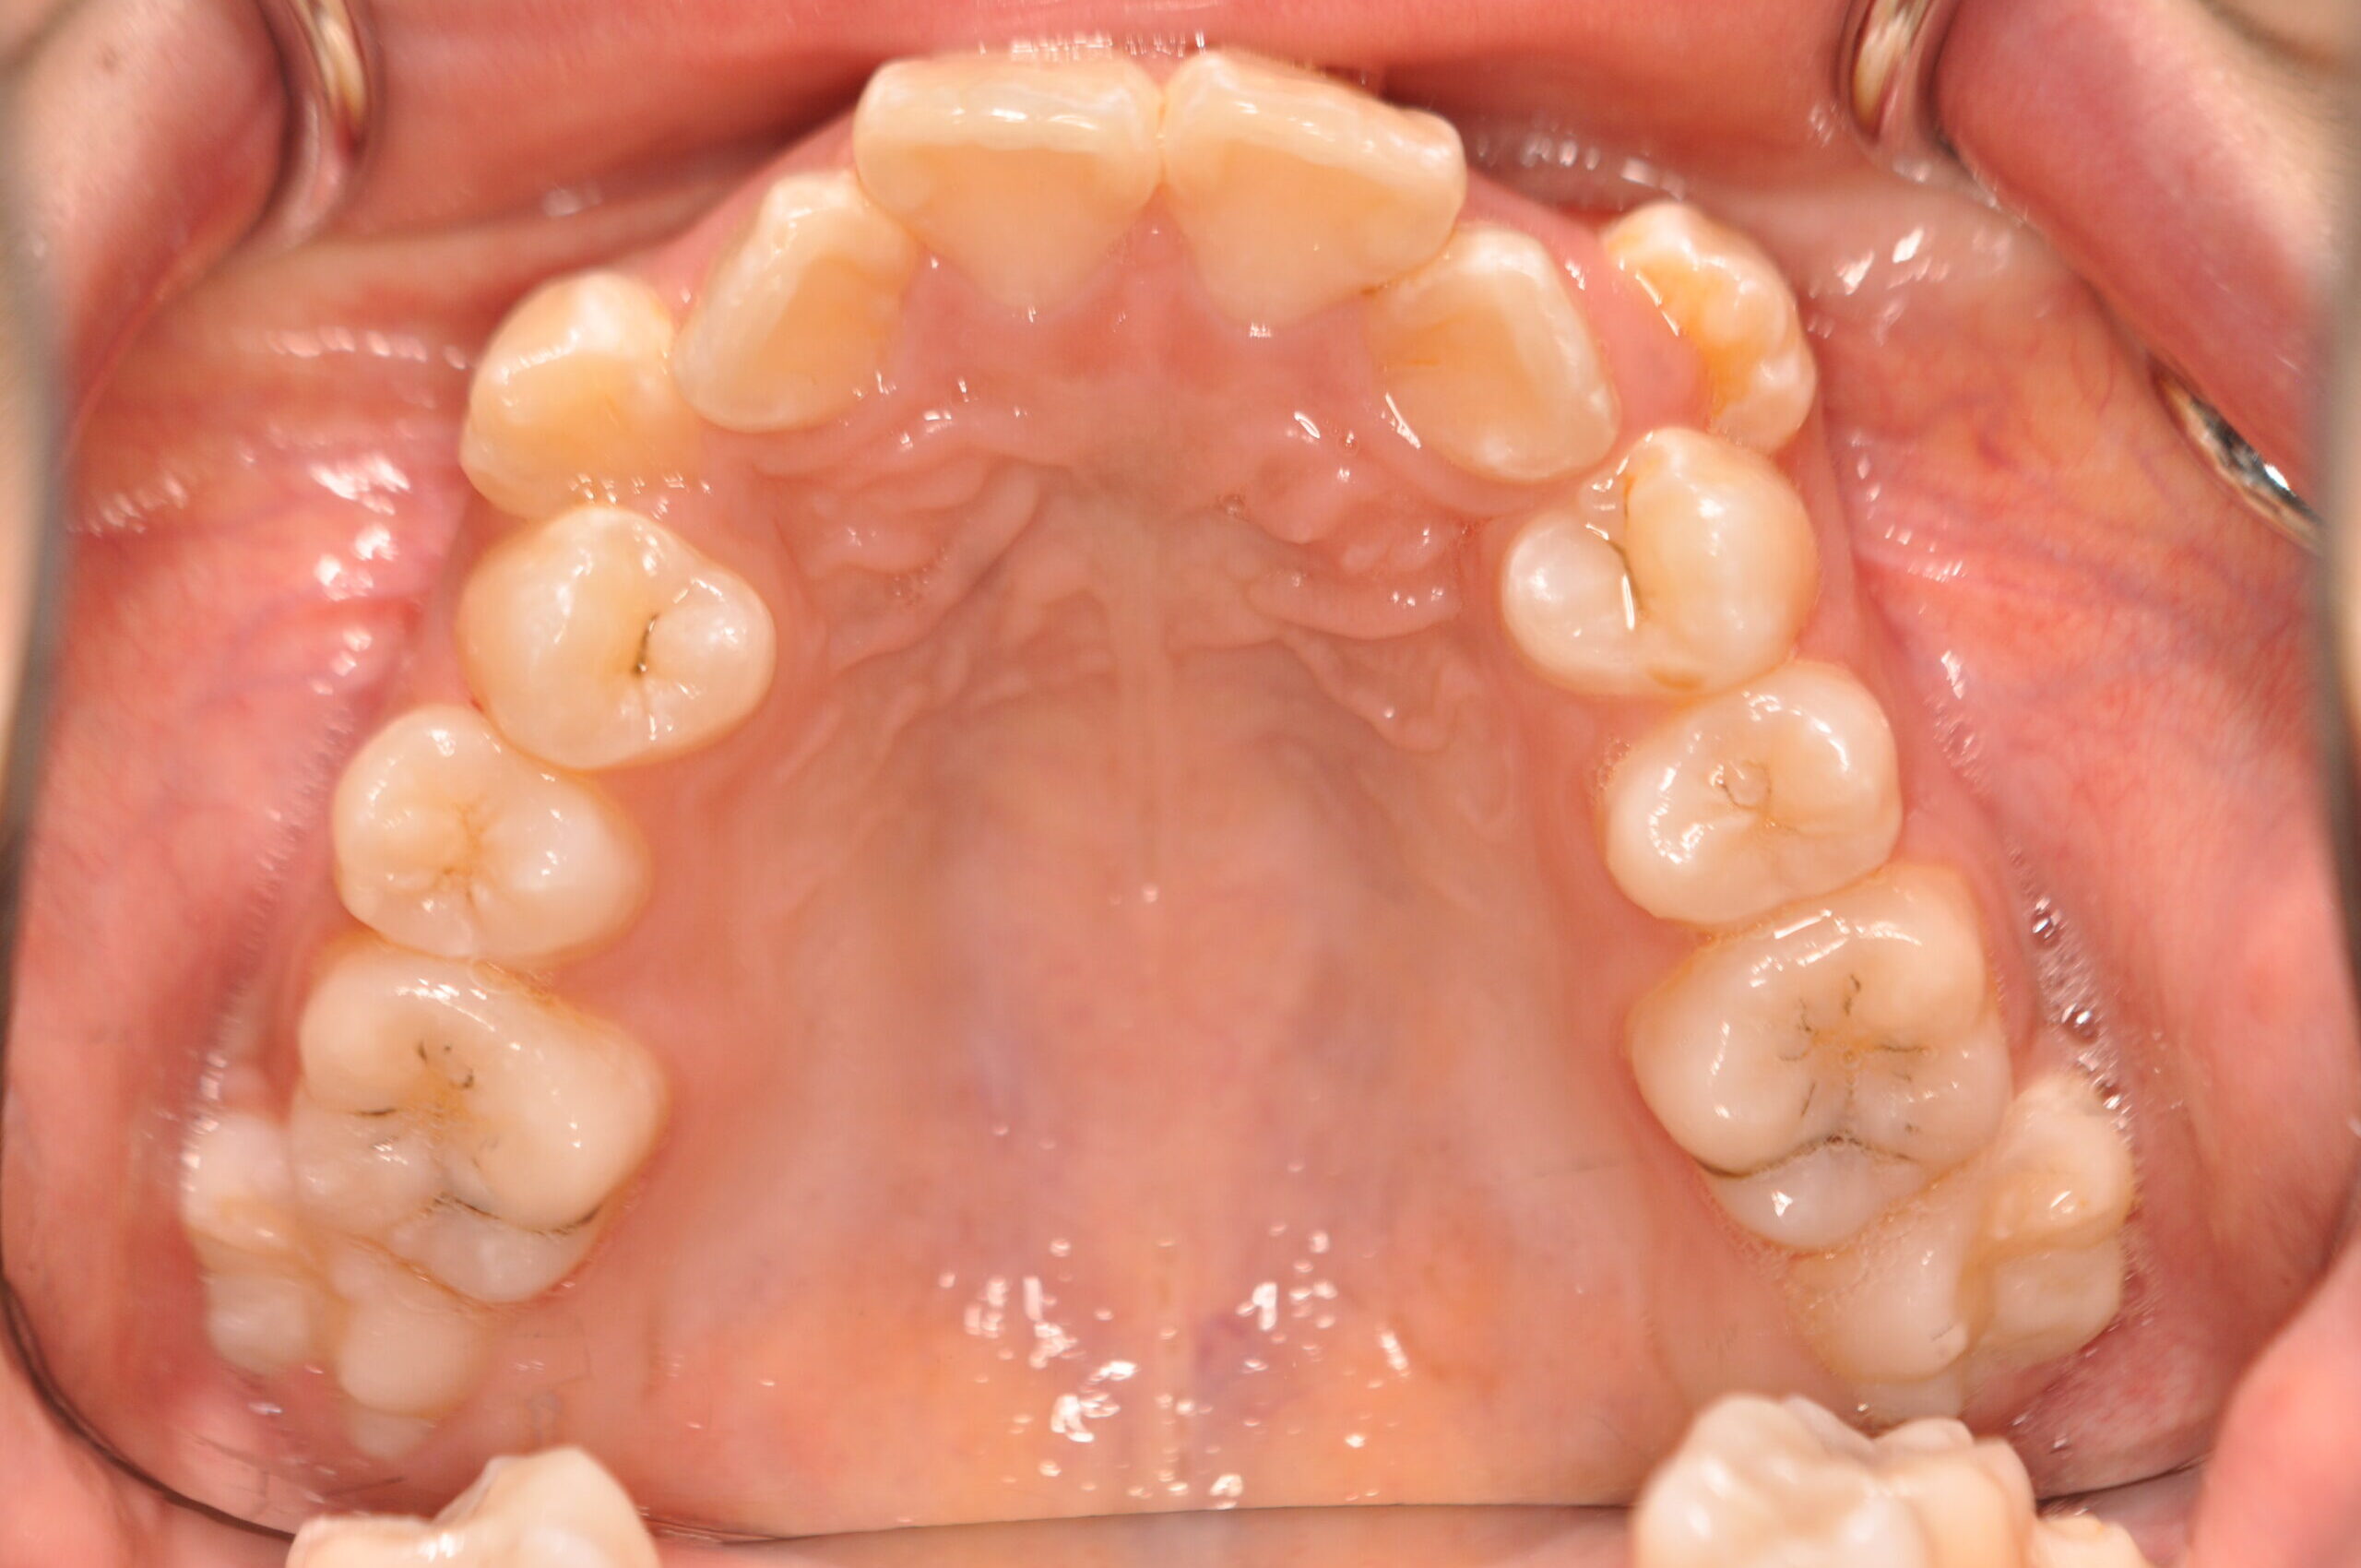

| 治療内容の詳細 | 初診時12歳の女性で、歯並びが悪く歯が磨きにくいことを気にされ来院されました。 検査の結果、上顎前突及び上下顎前歯部叢生を伴うアングルⅡ級1類不正咬合と診断しました。 治療としては、上顎左右第1小臼歯を抜歯し、セルフライゲーションブラケット装置(デーモンシステム)で歯の配列を行いました。 同時に顎間ゴムにて咬合関係の改善を行いました。 治療期間は、2年6ヶ月でした。 |